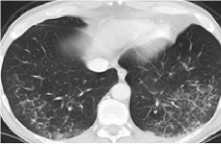

Примеры наиболее частых пульмонитов представлены на рисунке 1.

Пульмонит с участками матового стекла и консолидации, картина организующейся пневмонии (ОП)

Рисунок 1. Виды Л-ИЗЛ